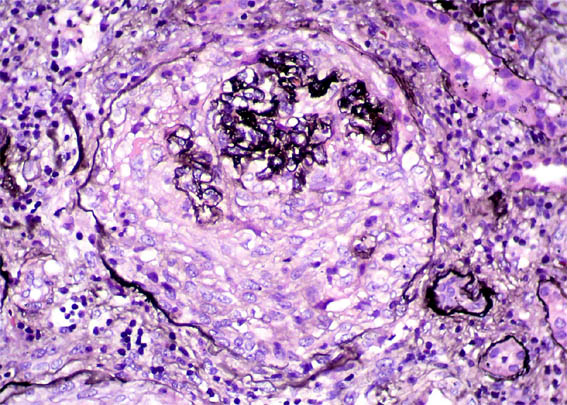

Figura 3. H&E, X400.